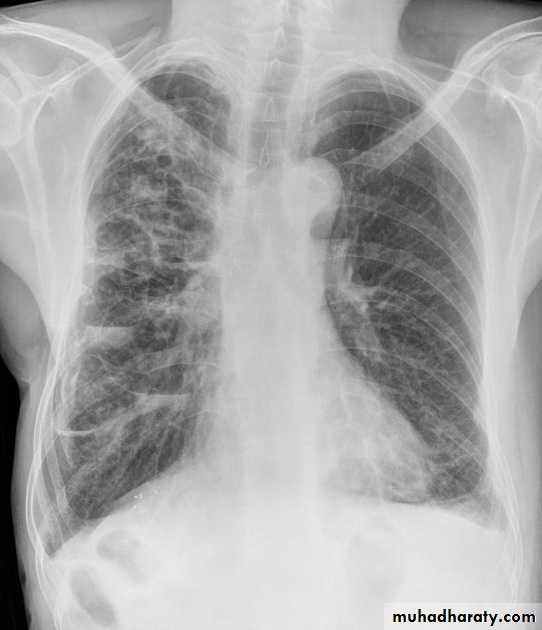

Lobular consolidation ( broncho or lobular pneumoniaCXR of adult ,PA and lateral views show:Patchy consolidation in both lung fields (diffuse) mainly in the lower zonesNormal heart size

Very important to consider that pulmonary edema in normal sized heart have close similar appearance to broncho pneumonia

The important Golden Key differentiation is the cardiac size being enlarged in pulmonary edema .